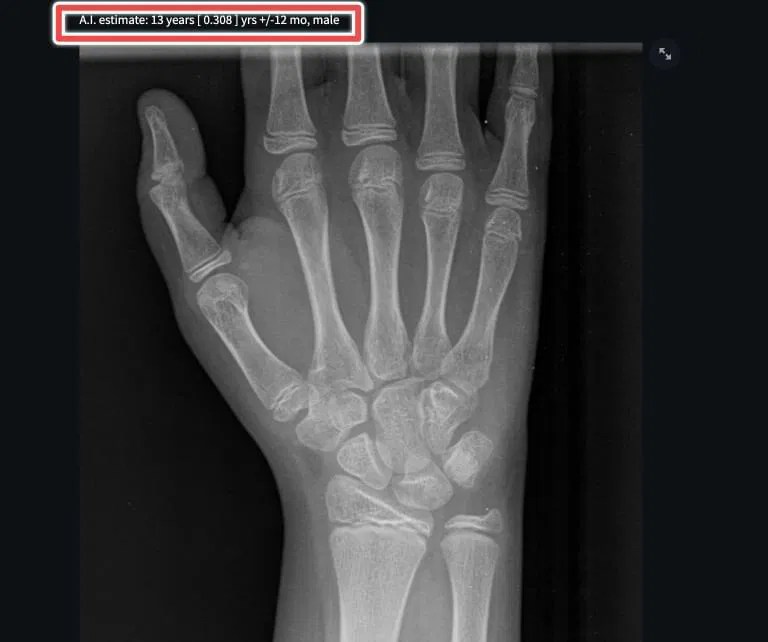

From radiogyan.com

Calculating Bone Age Using Xrays [Includes AIbased Automated Tools Bone Age X Ray Test Performing bone age assessments can assist clinicians in diagnosing central precocious puberty. A bone age study helps doctors estimate the maturity of a child's skeletal system. Puberty is a time for rapid. A bone age study helps doctors estimate the maturity of a child’s skeletal system. A bone age study helps doctors estimate the maturity of a child's skeletal system.. Bone Age X Ray Test.